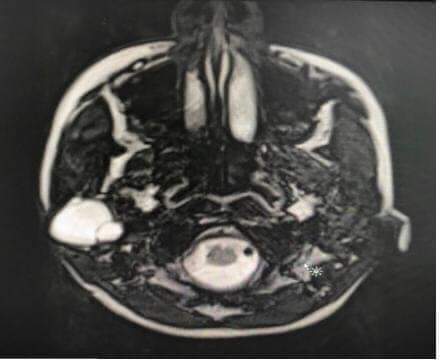

قام فريق جراحة الرأس والعنق من دائرة الأذنية برئاسة المقدم الطبيب صهيب المومني، بإجراء عملية جراحية لحالة نادرة جداً على مستوى العالم وذلك باستئصال أكياس كلبية من داخل غشاء العصب السابع المار في الغدة النكافية لفتاه عشرينية في مدينة الحسين الطبية، وباشراف مستشار اول جراحة الرأس والعنق الدكتور حسان الحسبان.

وأوضح المومني، بأن هذه الحالة تعتبر نادرة جداً على مستوى العالم حيث من المتعارف عليه  بأن الأكياس الكلبية تصيب الكبد والرئتين، وإضاف  وفي هذه الحالة وجدت الاكياس الكلبية داخل غشاء العصب السابع المار من الغدة النكافية، دون اصابة نسيج الغدة النكافية نفسه.

واشار الحسبان، بأن الفريق الجراحي إستئصال الجزء المصاب من العصب السابع المار في الغدة النكافية، من ثم قام بترميم العصب السابع بإستخدام جهاز تتبع العصب السابع والمكيروسكوب الجراحي، وذلك بتوصيل الفروع السليمة للعصب مع ما تبقى من جذع العصب بعد استئصال الجزء المصاب.